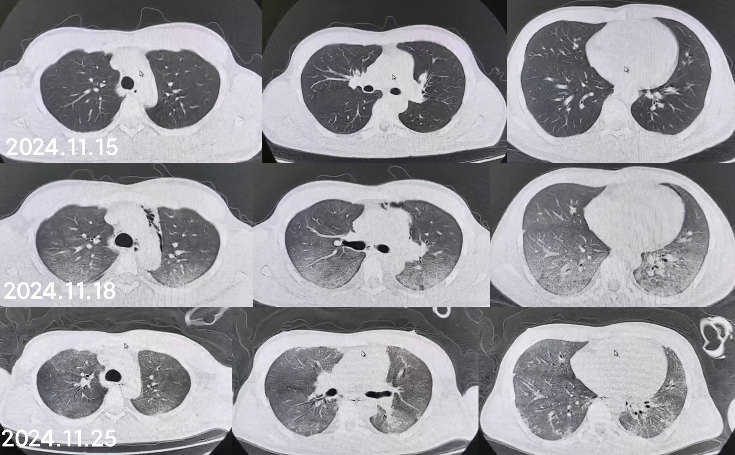

同时给予镇痛、镇静联合肌松,去甲肾上腺素泵入维持血压,俯卧位通气,B某入院后出现高热,经验性给予美罗培南联合万古霉素抗感染治疗,后降阶梯调整为哌拉西林他唑巴坦联合万古霉素治疗;C某抗感染方案为经验性使用万古霉素联合哌拉西林他唑巴坦治疗,痰培养出鲍曼不动杆菌后改为替加环素、头孢哌酮舒巴坦及万古霉素治疗;根据《刺激性气体中毒诊治专家共识》[5]中关于重症患者的治疗措施,同时给予2人泮托拉唑抑酸护胃,氨溴索、富露施化痰、甲泼尼龙抗炎、西维来司他纳及乌司他丁清除炎性介质,维生素C抗氧化、保肝、输血补液,纤支镜吸痰及肺泡灌洗,维持水电解质平衡及营养支持治疗,特别考虑到肺损伤情况,在使用有创通气时给予超保护性通气策略[5, 7];2人仍先后出现气胸、纵膈气肿,行胸腔闭式引流;持续V-V ECMO治疗15 d后,肺部纤维化不可逆转,高分辨率CT肺纤维化评分 > 75%(图 3、4),符合终末期肺病标准,有肺移植指征[8],经评估后2人顺利完成病变肺组织切除(图 5),双侧序贯肺移植,术后患者复查胸片肺部恢复正常(图 6),2位患者术后气管切管接呼吸机辅助通气,并给予泼尼松、他克莫司、吗替麦考酚酯抗排异治疗,其余根据病情给予万古霉素调节肠道菌群、抗感染、保肝、抗凝、呼吸康复锻炼等治疗,后顺利脱机、拔除气切套管,病情稳定出院,后续规律复查胸部CT(图 7)恢复良好。

| 注:图A为B某;图B为C某 图 7 肺移植术后第2个月、5个月、8个月CT影像 |